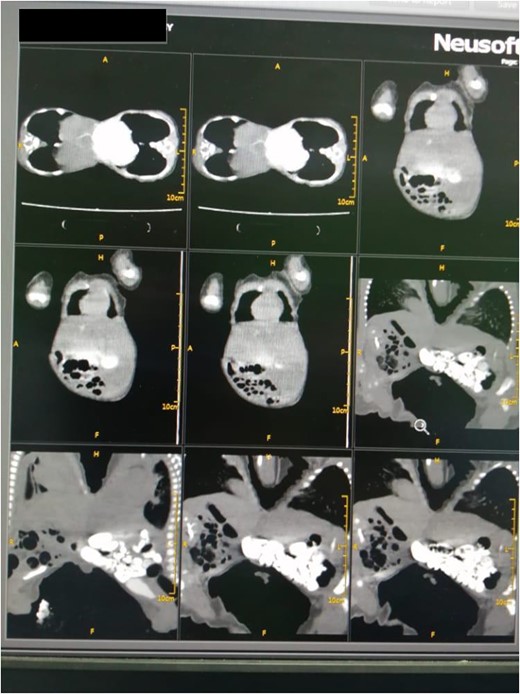

Following the placement of central lines, the two babies were anathesized and stabilized with vital sign monitoring and fluid adjustments. Then, using monopolar and bipolar diathermy, incisions and flaps were made until the peritoneum, where complete fusion of the liver with a sinusoidal connection was discovered. The connected surface area is ⁓8 by 6 cm, primarily in the caudal lobe, whereas twins B has one lobe liver and one gall bladder (Fig. 4). The xiphoid process, sternum, pleura and pericardium were all visible in the patient and were successfully separated. To avoid the occurrence of compartment syndrome, the abdomen was left as a shallow cavity with only skin closed as a neonatal hernia, then hemostasis was secured via PDS sutures and drains were placed, admitted to neonatal intensive care unit and received blood and fresh frozen plasma. The patients recovered well from anesthesia on the second day, were taken off mechanical ventilation with normal vital signs, and began Nasogastric tube tube feeding 48 h later. Patients began to gain weight and were discharged the next day to be seen at a referral clinic.